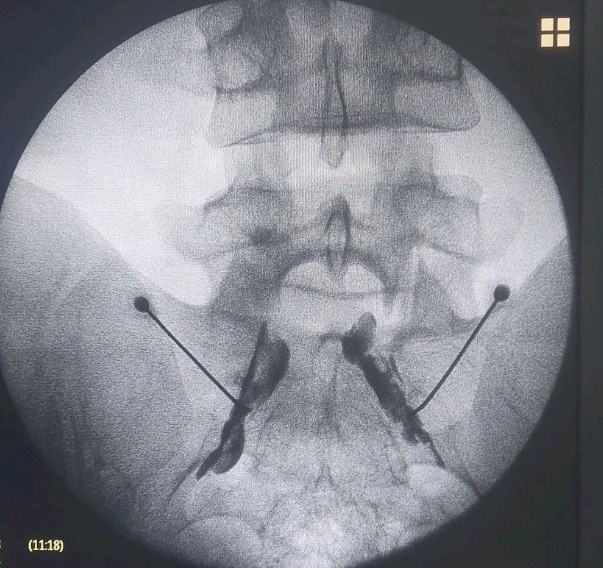

- Διατρηματική επισκληρίδιος έγχυση

- Διέγερση της ρίζας με παλμική ραδιοσυχνότητα σε περιπτώσεις μετεγχειρητικής ισχιαλγίας